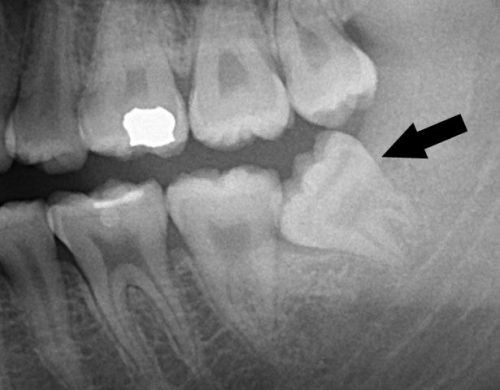

Có những người không quan sát được răng khôn mọc lên nhưng thực tế có thể vẫn có răng khôn mọc lệch hoặc mọc ngầm ở dưới xương hàm và bị mô mềm che phủ. Răng số 8 bị mọc lệch gây ra rất nhiều biến chứng ảnh hưởng đến sức khỏe răng miệng và sức khỏe toàn diện của cơ thể người bệnh.

Răng số 8 mọc lệch thường làm hỏng răng bên cạnh là răng số 7. Tình trạng mọc lệch hình thành nên khe hở giữa răng khôn và răng số 7 dễ làm kẹt lại thức ăn, khiến khó vệ sinh, lâu ngày chắc chắn gây ra sâu răng. Khi răng khôn mọc lệch làm ép vào răng bên cạnh làm tiêu biến mất một phần thân và chân răng này.

Quá trình tổn thương có thể diễn ra trong âm thầm kéo dài trong nhiều năm, và cho đến khi bạn phát hiện ra thì tổn thương đã lan rộng gây biến chứng nặng. Khi đi đến phòng khám kiểm tra thì đôi khi răng số 7 đã bị hỏng, hư hại nặng không thể giữ lại được.

Trong khi đó bạn cần phải biết rằng răng số 7 (hay còn gọi là răng hàm lớn thứ hai) là một trong những răng giữ chức năng ăn nhai quan trọng nhất ở trên cung hàm.